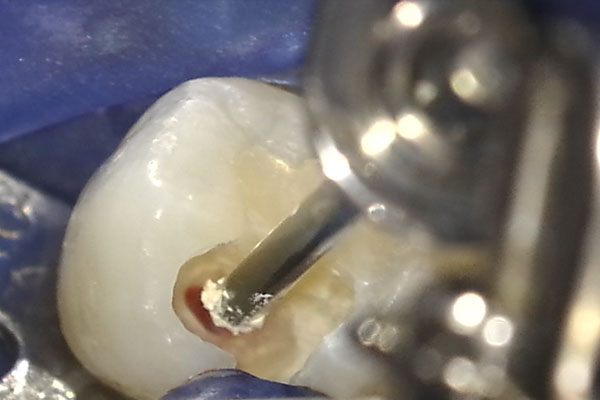

7.虫歯は神経の中まで進行していました

虫歯を取り切ると、最も深いところから神経が露出しました。この時点で神経から出血がないと、すでに弱って大半が死んでしまっているため、除去する治療に方針を転換します。本症例では、新鮮な出血があり神経は生きていると判断しました。